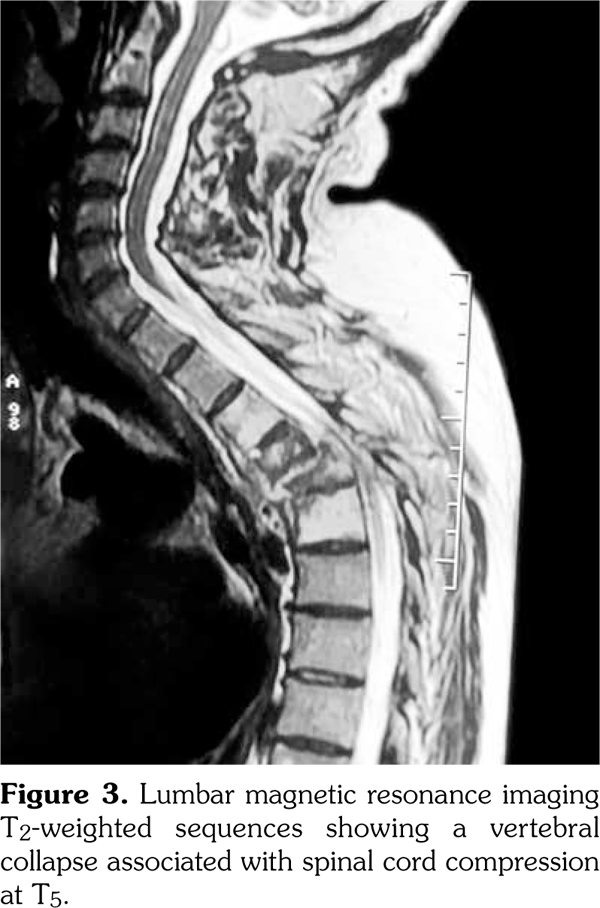

Thus, the diagnosis of SAPHO syndrome was established. Despite the use of nonsteroidal antiinflammatory drug, the disease remained active as attested by Bath Ankylosing Spondylitis Disease Activity Index at 6.7 at three-month follow-up. Then, the patient was lost to follow-up. One year later, he presented with hypesthesia and muscle weakness of his lower limb associated with kyphotic deformity and sphincter symptoms. He was unable to walk. Magnetic resonance imaging showed a vertebral collapse associated with spinal cord compression at T5 (Figure 3). Surgical treatment based on decompression and reconstruction with screw fixation was performed (Figure 4). The histopathology of the specimen obtained surgically showed nonspecific osteomyelitis with an infiltration of inflammatory cells and abnormal fibrous hypertrophy among the trabecular bone. One year later, etanercept was administered at a dose of 50mg weekly, leading to complete resolution of articular manifestations. Clinical remission was obtained under etanercept (Bath Ankylosing Spondylitis Disease Activity Index at 2.1). After two years of follow-up, patient’s paralysis improved by surgery, and he was progressively able to walk.